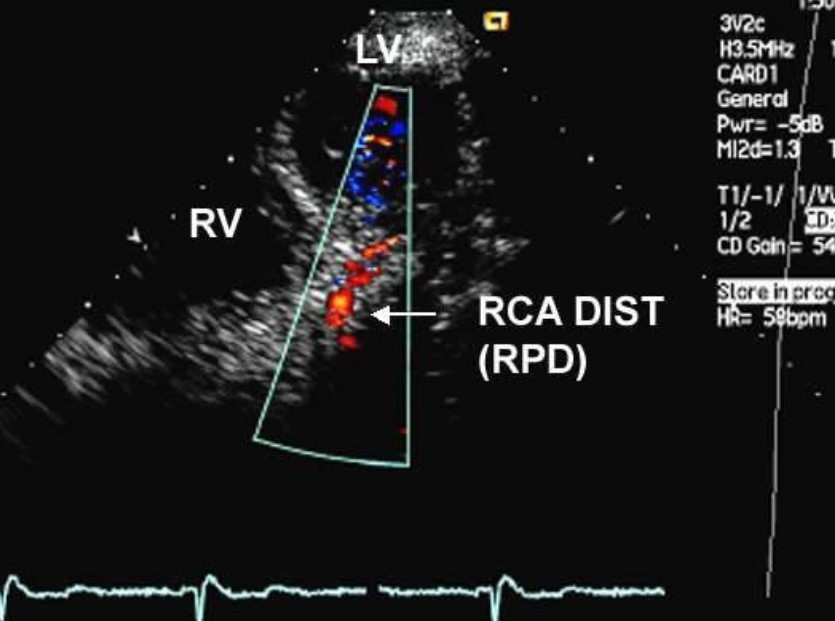

Najważniejszy cel badania to ocena przepływu w:

• gałęzi przedniej zstępującej (LAD) – najczęściej analizowany odcinek,

• czasem także w:

• gałęzi okalającej (Cx),

• tętnicy wieńcowej prawej (RCA),

• gałęzi tylno–zstępującej.

Na ekranie widać:

• kolorowy sygnał przepływu w tętnicy,

• a w trybie Dopplera pulsacyjnego – wykres prędkości przepływu w czasie, z dominacją fazy rozkurczowej (bo właśnie w rozkurczu wieńcówki „naprawdę” dokarmiają serce).

3. Ograniczony zasięg – głównie LAD

W praktyce:

• najłatwiej ocenić LAD,

• pozostałe tętnice (RCA, Cx) udaje się dobrze ocenić u mniejszej części chorych.